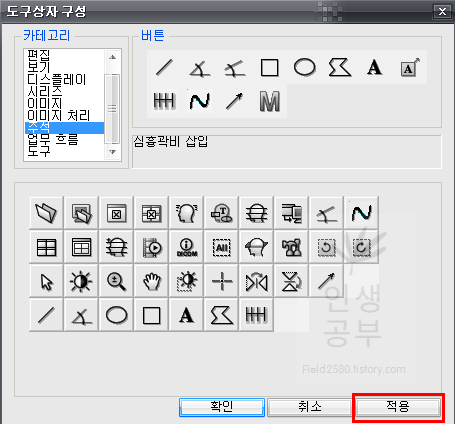

위와 같은 도구상자 구성 화면이 뜨게 됩니다. 아래에는 현재 사용중인 도구상자들이고 왼쪽 상단에는 도구상자에 넣을 수 있는 카테고리들이 있습니다. 카테고리칸 옆에는 버튼칸이 있고 아래 도구상자칸에 없는 메뉴들도 많이 있습니다. 아이콘에 마우스를 가져다 대면 간단한 설명이 나오니 필요하신 분들은 한번씩 다 확인해보시는 걸 추천해드립니다.

저 같은 경우는 Cobb 각도를 많이 사용하기 때문에 우선 Cobb각도 설정하는 방법에 대해서 알려드리겠습니다. 카테고리칸에 주석을 눌러주면 다양한 각도나 선, 모양을 그릴 수 있는 버튼이 나옵니다. 그중 상단 3번째 있는 버튼이 Cobb각도 그리기 입니다.

Cobb각도 그리기 버튼을 클릭해주고 아래로 쭉 내려주면 현재 사용하고 있는 도구상자에 Cobb각도 그리기 버튼이 추가되는 것을 확인하실 수 있습니다.

카테코리에 있는 모든 버튼을 보시는 것을 추천합니다. 위에 설명해드린 것은 제가 환자들과 함께 X-ray보면서 많이 사하는 것들이니 사용자에 따라서 선호하는 것들이 다를 수 있으니 한번 모두 다 보시고 추가할 것들은 추가하고 제거할 것들은 제거해주시는 것이 좋습니다. 카테고리에 있는 메뉴를 누르면 해당 메뉴에 버튼이 나오게됩니다. 이 버튼에 마우스를 가져대면 아래에 짧은 설명이 나오니 참고해주시기바랍니다. 어짜피 시간이 지나면서 잘 안쓰는 것들은 삭제하게 되니 필요에 따라서 삭제할 수도 있고, 필요한 것들은 다시 추가할 수 있으니 너무 많이 고민하지 않으셔도 됩니다. 본인에 맞게 메뉴가 세팅이 되었으면 적용버튼을 눌러줍니다.

본인에게 맞는 도구상자가 구성 되었으면 적용버튼을 눌러줍니다.